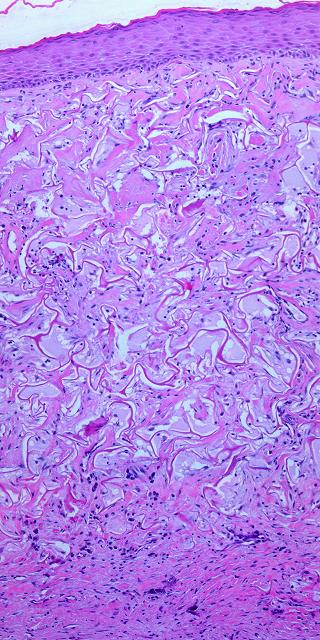

Figure 3

These five images demonstrate the absence and suppression of inflammation.  Figures 3a, b, c were taken from a patient having lower extremity dermatofasciectomy for primary lymphedema (Milroy’s, praecox).

(3a, top left)  Biopsy was taken 4 hours after the fasciectomy, just prior to Integra.  Normal post-traumatic thrombosis has recognized the injury, attracting polymorphonuclear leukocytes (neutrophils) which are densely marginated in blood vessels on the wound surface.  This is the normal response to injury, the start of inflammation.

(3b, top right)  Biopsy was taken 4 hours later after placing Integra.  A blood vessel is present at the wound surface between Integra matrix (top and left) and normal adipose (bottom and right).  Leukocyte margination and migration are present, but not dense

(3c, middle, left)  At 24 hours the only neutrophils are a few, in proportion to the red cells that bled into the matrix.  Figures 3d, e are from a similar patient.

(3d, middle, right)  At 5 days, the only cells present are early histogenetic pioneer and transitional cells.  There are no neutrophils, no plasma cells, no eosinophils, no lymphocytes, no monocyte-macrophages.  Other than some late foreign body giant cells occurring along the silicone, at no time does a defensive response ever appear in the matrix.

(3e, bottom)  At 11 days, the matrix remains mostly devoid of cells in this locale, although the entrainment of cells starting to migrate toward the matrix is apparent at lower right.  (Note 1:  Cell migration and histogenesis occur casually at different rates throughout the matrix, and it is common that a somewhat later image (3e at 11 days) might appear less populated than an earlier image from a different area (3d at 5 days);  this variability of time with Integra is the norm.  Note 2:  Unless otherwise stated or obvious, all histological images presented throughout the chapter are oriented with the outer superficial surface, silicone or epidermis, at the top.)